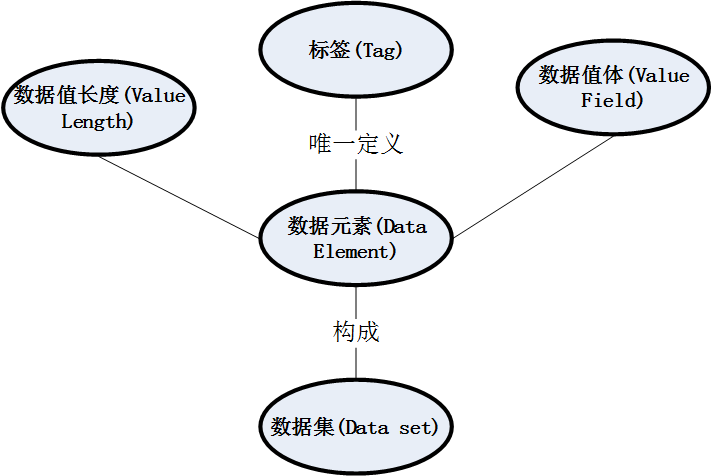

.dcm文件里面的数据结构大致如下:

.dcm文件相应的数据存储结构可参照论文:

《DICOM 数据集与 DCM 文件格式》全海英, 杨源, 张歆东, 郭树旭, 刘景鑫

简单来说,一个.dcm格式的文件中,包含了一个数据集(Data set),由如下代码获取这个数据集:

.dcm文件就像一个容器,而数据集才是真正的内容。

在数据集(Data set)中,包含了文件的元信息(Meta Information,存储了被封装数据集的标识信息)以及数据元素(Data Element);通过调用相应的函数来获取文件的元信息以及数据集,代码如下: